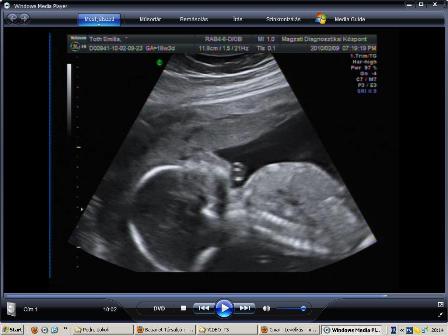

Leszedtem, a dvd-ről a fütyi+zacsi bizonyítékunkat, hogy megmutizzam :D:D:D:D

Igaz csak 2D, de jól látszik a fütyi és a zacsi is 16+6 hetesen :)